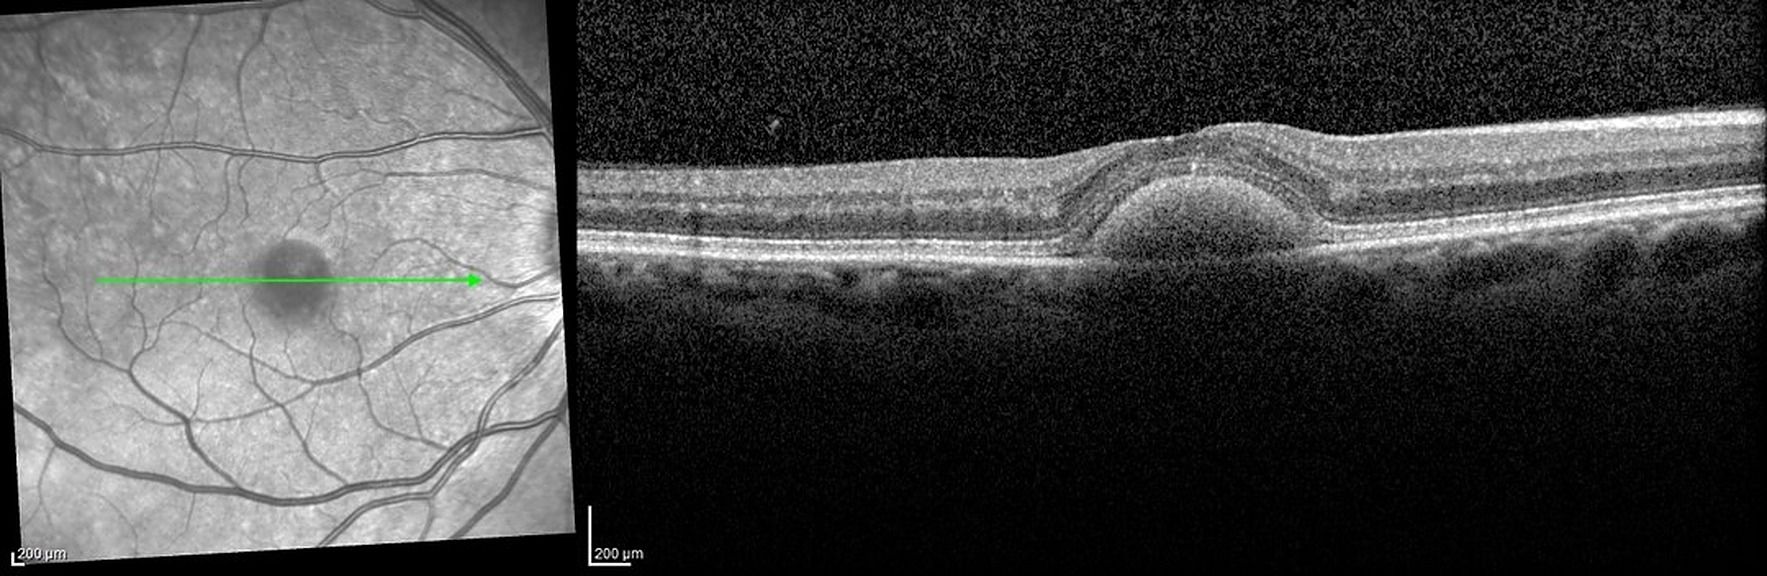

Les dystrophies maculaires héréditaires, quels examens pour orienter le diagnostic ?

Les dystrophies maculaires héréditaires peuvent être rencontrées en consultation ophtalmologique. Savoir les identifier et surtout savoir prescrire et réaliser les bons examens complémentaires à leurs diagnostics est essentiel pour la prise en charge de ces patients souvent jeunes.